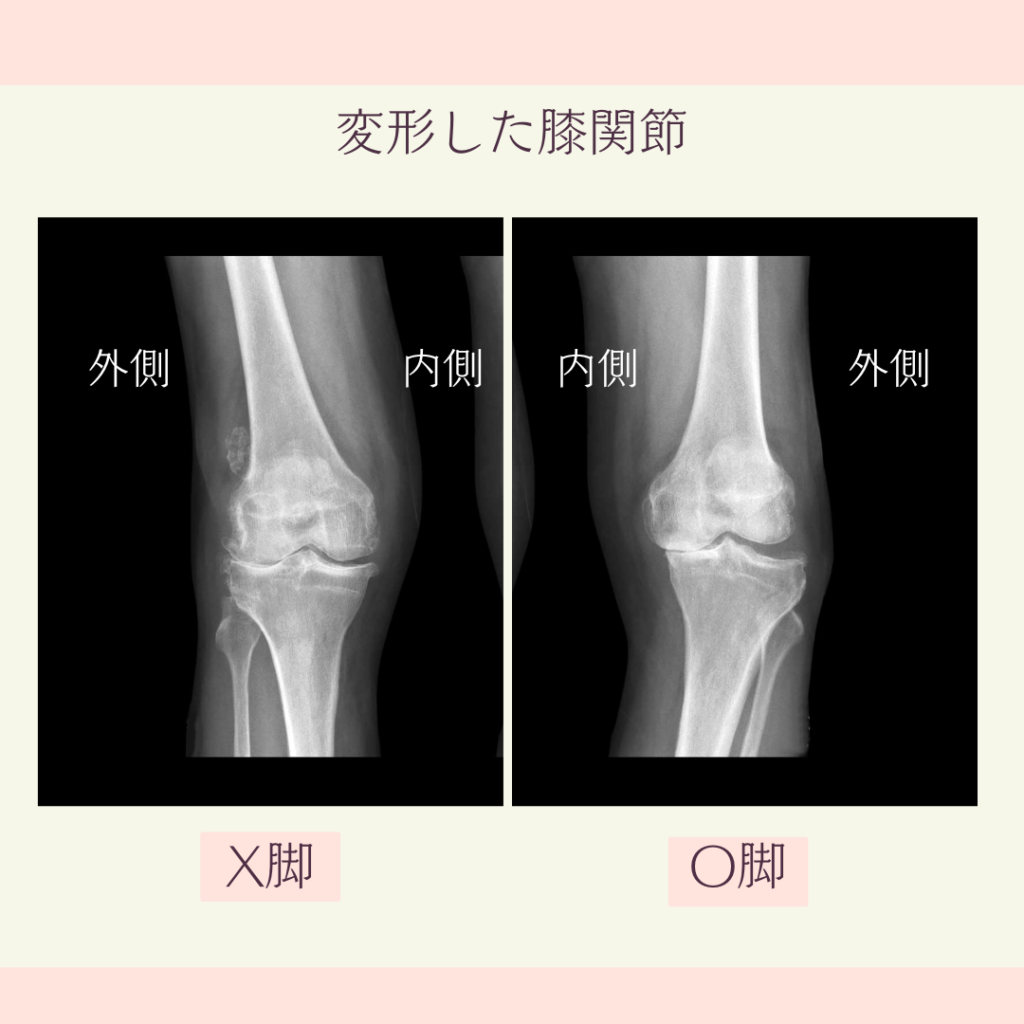

どちらの膝関節もすき間が不均衡で

片側の関節面がくっついています。

このような状態で

膝の曲げ伸ばしを繰り返していくと

常に 片側だけの関節面に強く圧がかかり

半月板や関関節軟骨が 擦れてしまします。

そうして段々とすり減ってしまいます。

これらがすり減り無くなると

強い痛みで歩けなくなり

人工膝関節の手術が 必要となります。